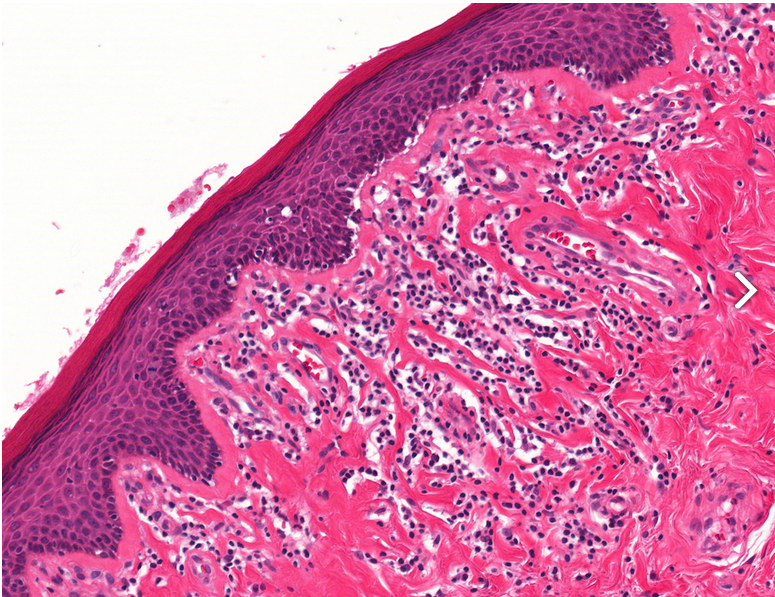

Lichen Sclerosis

Basal vacuolation seen just above the linear sclerosis of the basal membrane.